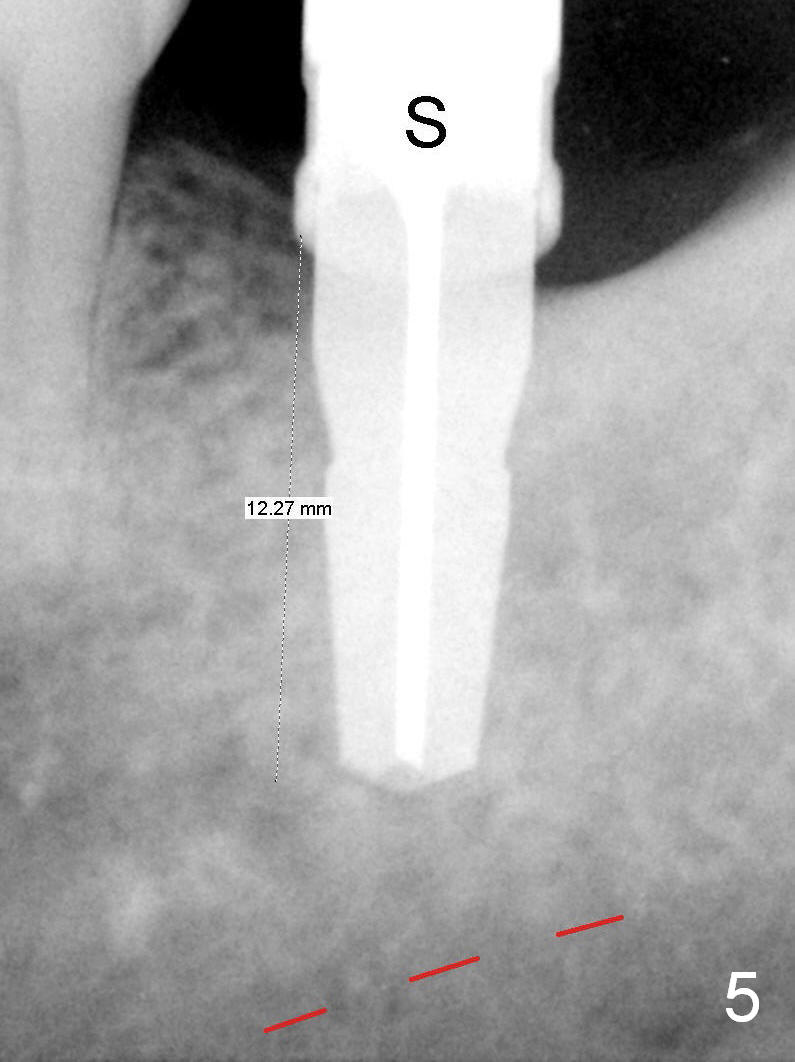

A 48-year-old lady is a dental phobic, requesting extraction of the lower left 2nd molar (Fig.1). She returns for implant placement 9 months post extraction (Fig.2). The ridge is mildly to moderately atrophic. It appears that a 5x12 mm implant is appropriate for the site (Fig.3). For safety, osteotomy is initiated at the depth of 10 mm; it appears that there is enough height for a 12 mm implant (Fig.4). The depth is controlled by drill stopper (Fig.5 S). Finally a 5x12 mm implant is apparently safely placed (Fig.6). A healing abutment is placed and the incision is sutured with 4-0 Chromic gut (Fig.7). Perio dressing is applied around the healing abutment for wound protection (Fig.8). It appears that the healing abutment (Fig.8': *) helps stabilize the perio dressing, which remains in place 1 week postop. When the perio dressing is removed, the wound around the healing abutment is healing (Fig.9). There is no bone loss around the implant 3 months postop (Fig.10 (H: healing abutment), or 16 months postop (i.e., 9 months post cementation, Fig.11,12). The patient complains of pain when she chews with the implant crown, but pain stops whenever she does not bite. Percussion does not elicit any discomfort. The gingiva is healthy. There is possibility of the buccal plate being thin or the lingual plate being perforated in the submandibular fossa. If the discomfort remains the same next 6 months, CBCT will be prescribed.